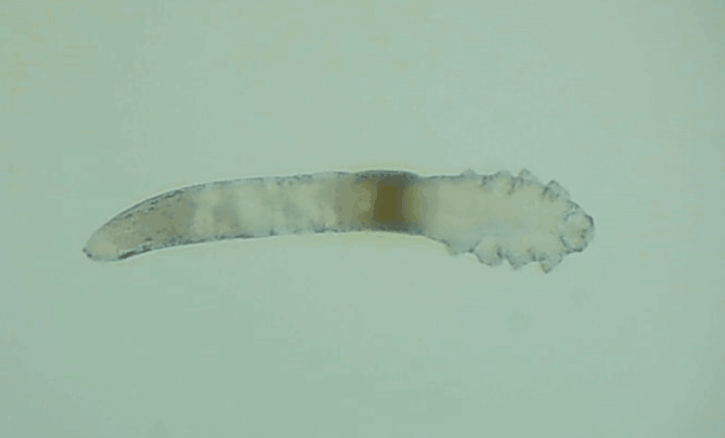

其實(shí)蠕形螨主要活動(dòng)在毛囊和皮脂腺中,以皮膚碎屑和腺體分泌物作為食物來源,而睫毛根部的瞼板腺是排泄油脂的重要部位,因此眼睫毛和瞼板腺也是螨蟲的主要活動(dòng)場所。

一般來說,15天內(nèi),一只蠕形螨會(huì)在你眼睛里產(chǎn)下50只蟲卵。如果不及時(shí)除螨,它們會(huì)迅速繁殖,從而導(dǎo)致睫毛脫落、亂生、眼睛紅癢,甚至引發(fā)眼部炎癥。如果影響到角膜,就會(huì)造成視力下降甚至失明。